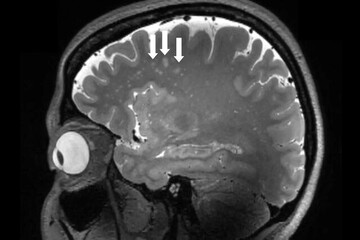

اکنون یک مطالعه با استفاده از فناوری تصویربرداری پیشرفته برای به دست آوردن دیدگاه جدیدی در مورد ساختارهای مغز انجام شده است که فضاهای بزرگ در اطراف رگهای خونی را در افرادی که از این بیماری رنج میبرند، نشان میدهد و بینش مهم جدیدی را برای این موضوع فراهم میکند.

تمرکز این مطالعه بر روی فضاهایی است که به عنوان فضاهای اطراف عروق شناخته میشوند که شکافهایی در اطراف رگهای خونی هستند که به پاکسازی مایعات از مغز کمک میکنند. بزرگ شدن این فضاها قبلاً با بیماری عروق کوچک مرتبط بود و مواردی مانند التهاب و ناهنجاری در سد خونی مغزی میتواند بر شکل و اندازه آنها تأثیر بگذارد.

از جملهی این تغییرات، خونریزیهای کوچک مغزی، همراه با بزرگ شدن فضاهای اطراف عروق در ناحیه مرکزی سِمیاُوال(centrum semiovale) در مغز مبتلایان به میگرن بود.

ژو میگوید: در افراد مبتلا به میگرن مزمن و میگرن اپیزودیک بدون هاله، تغییرات قابل توجهی در فضاهای اطراف عروق ناحیهای از مغز به نام centrum semiovale وجود دارد. این در حالی است که این تغییرات تاکنون هرگز گزارش نشده بود.